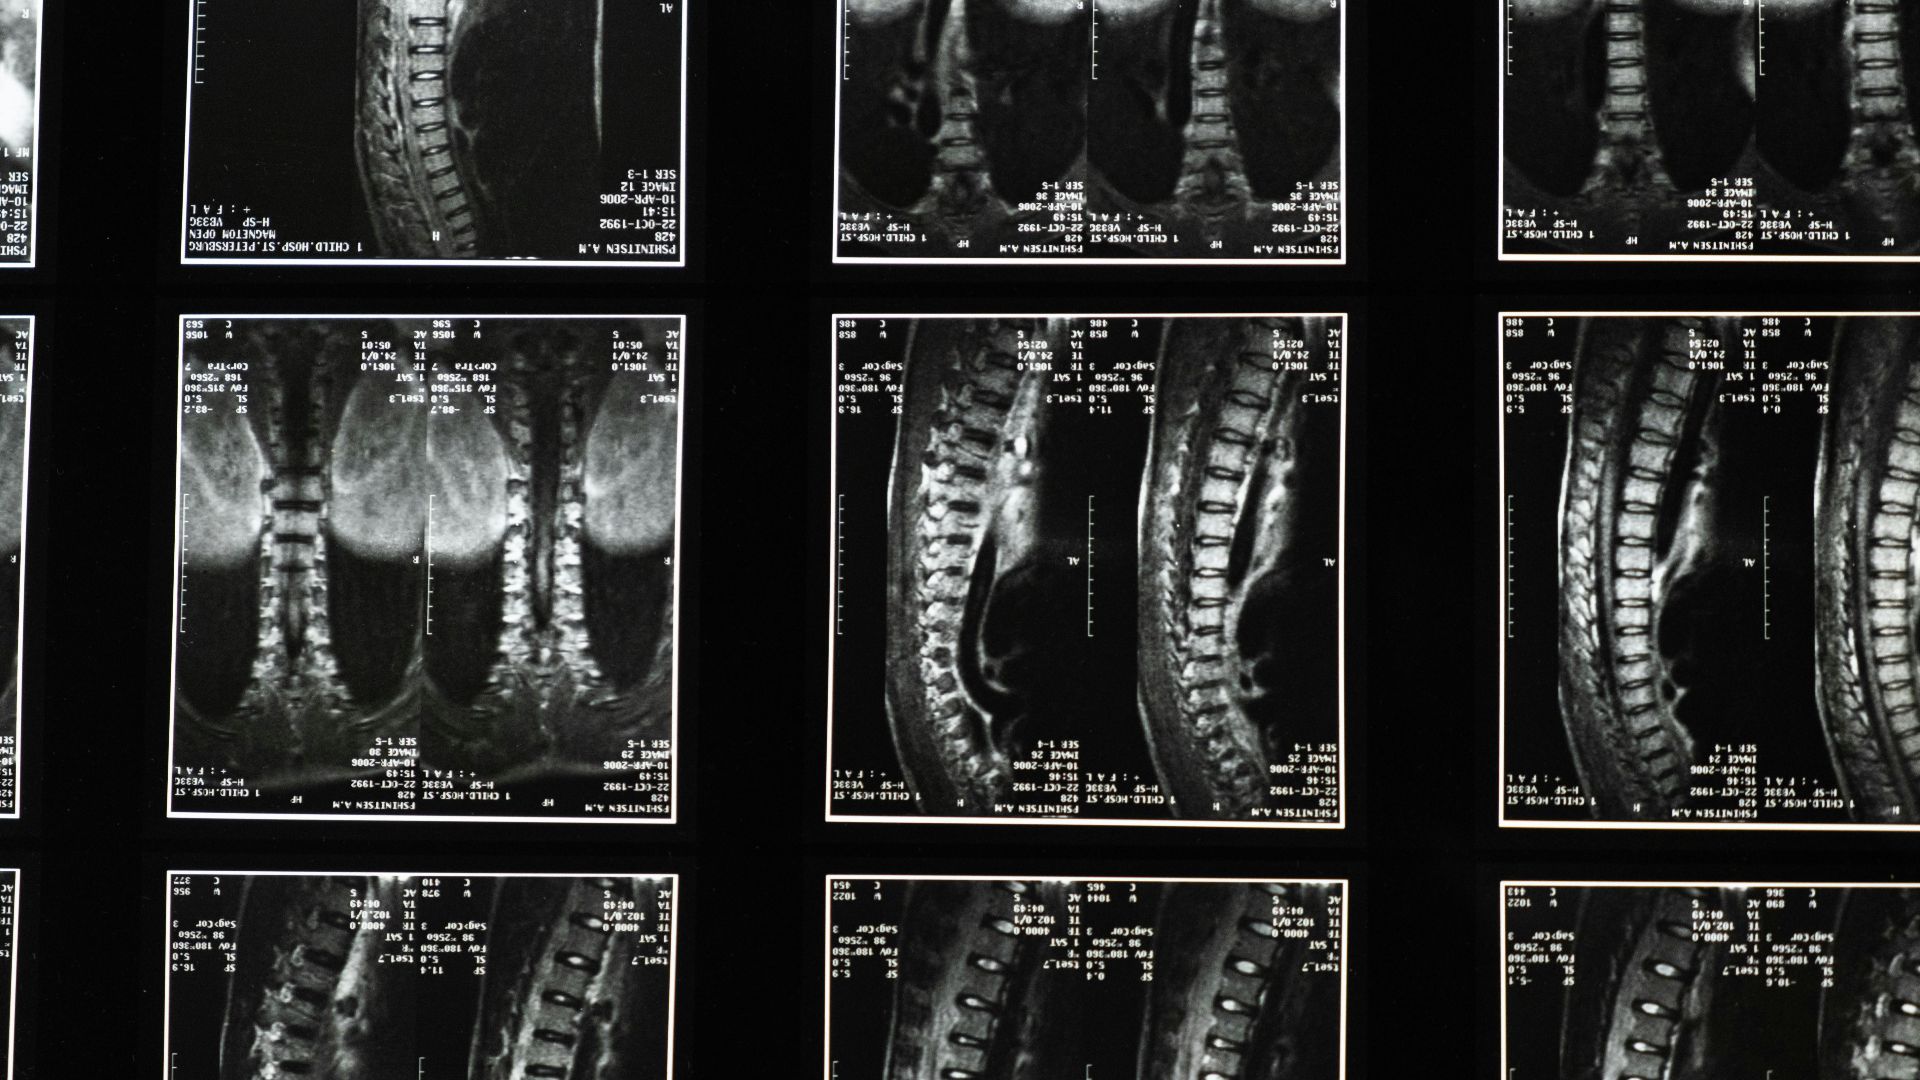

4. Spinal Muscular Atrophy

Spinal muscular atrophy is a rare genetic neuromuscular disease that effects neurons in the spinal cord and brainstem. It's characterized by muscle weakness and may lead to loss of movement.